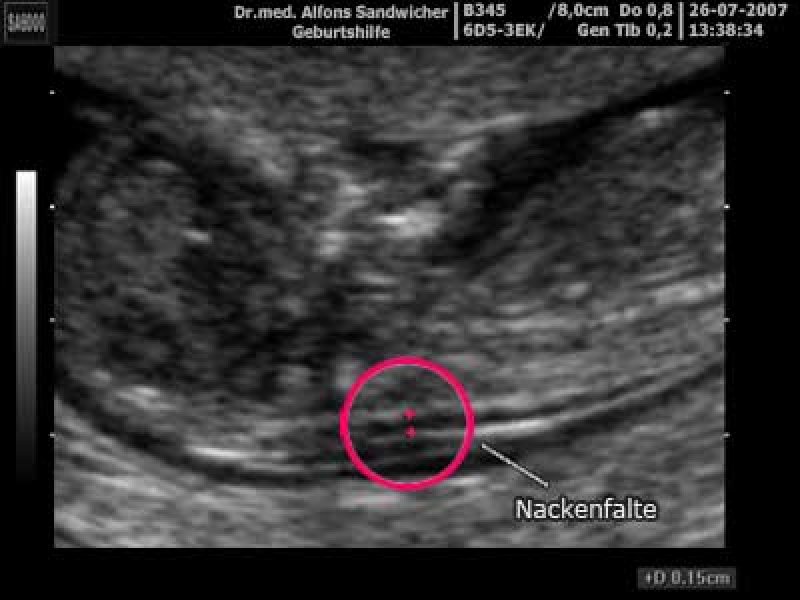

Trisomie Diagnosen sind oft mit einem Nackentransparenzwert ab 3 mm verbunden. Die Nackenfaltenmessung ist eine sichere und nicht-invasive Untersuchung, die viele wertvolle Informationen über die Gesundheit des Ungeborenen liefern kann

Source: tonchavrq.pages.dev Nackenfaltenmessung Mamiweb.de , Die Nackenfaltenmessung kann frühzeitig Hinweise darüber geben, ob mit Eurem Baby alles in Ordnung ist. Messwerte zwischen 1 bis 2,5 mm liegen bei der Nackenfaltenmessung im Normalbereich

Source: targimgim.pages.dev ErstTrimesterScreening Frauenarzt in Gummersbach Steffen Maus , Ab 3 mm sprechen Ärzte von deutlich, ab 6 mm von starkt erhöht Dabei spielt aber auch die Größe des Babys zum Zeitpunkt der Untersuchung eine Rolle.